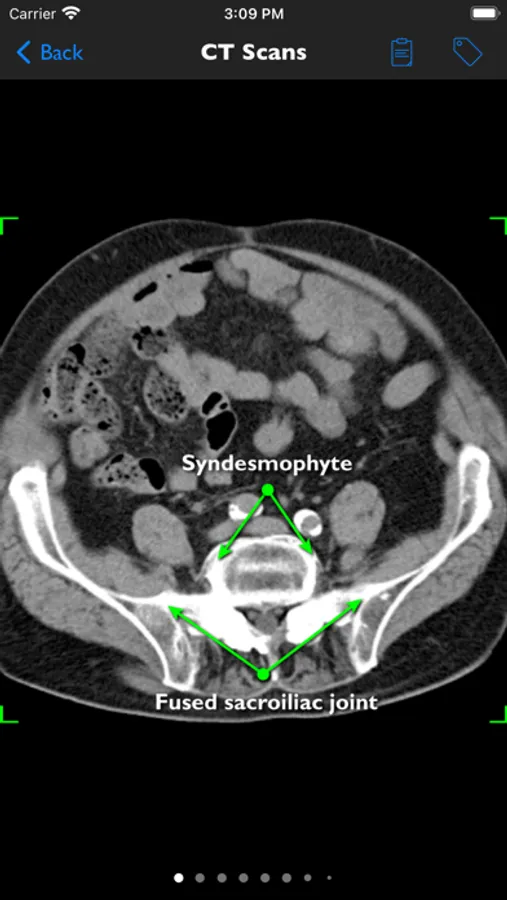

• detailed information on history, physical examination, assessment tools (printable), differential diagnosis, laboratory studies, histology and a medical imaging library of over 400 Xrays, CTs and MRIs